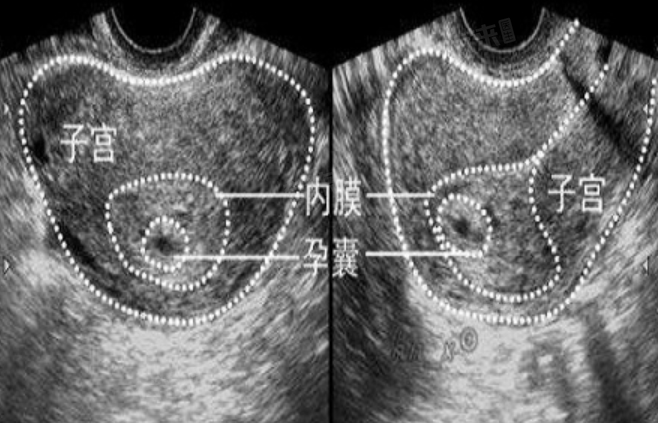

- 孕囊张力差通常指孕囊在B超检查中呈现出的形态不规则、张力不足的状态,可能由于多种因素引起,包括胚胎发育异常、黄体功能不全、子宫环境不佳、孕妇自身疾病以及不良生活习惯等。胚胎发育异常是其中较为常见的原因之一,可能涉及染色体异常或其他发育缺陷。

- 通过B超检查如果孕囊内能够逐渐出现胎心和胎芽,并且胎心搏动正常,那么说明胚胎发育良好,保胎治疗可能有意义。孕妇的年龄、身体状况、营养状况等也会对保胎的决策产生影响,如果孕妇身体状况良好,没有其他严重疾病,保胎治疗可能更加可行。

1、妇产科:妇产科是首要就诊科室,医生会详细询问患者的月经周期、受孕情况等病史,进行妇科检查,查看子宫大小、位置及附件状况。通过超声检查,进一步观察孕囊形态、大小及周边血流,判断是否存在先兆流产、胚胎发育异常等情况,为后续治疗提供依据。